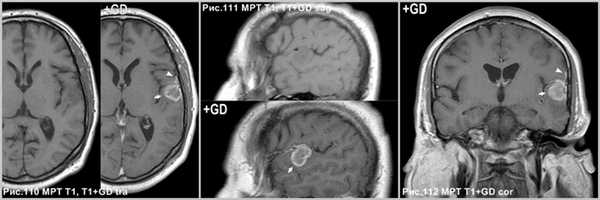

ПКА интенсивно накапливает контрастный препарат (стрелки на рис.110, 111 и 112). “Дуральный хвост” характерная особенность ПКА (головки стрелок рис.110, 112). Стенка кисты опухоли интенсивно накапливает контраст (стрелки на рис. 113-115).

Неравномерное и неоднородное накопление контрастного препарата. Может наблюдаться отсутствие контрастирования некоторых участков стромы опухоли. Патогномонично контрастирование прилежащей ТМО ("дуральный хвост") - как признак инфильтрации мозговых оболочек [2], Другое мнение, что это реактивные изменения, а не следствие прямого дурального вторжения, которое бывает редко [148]. Стенки кисты могут быть усилены или не накапливают контрастный препарат [48].